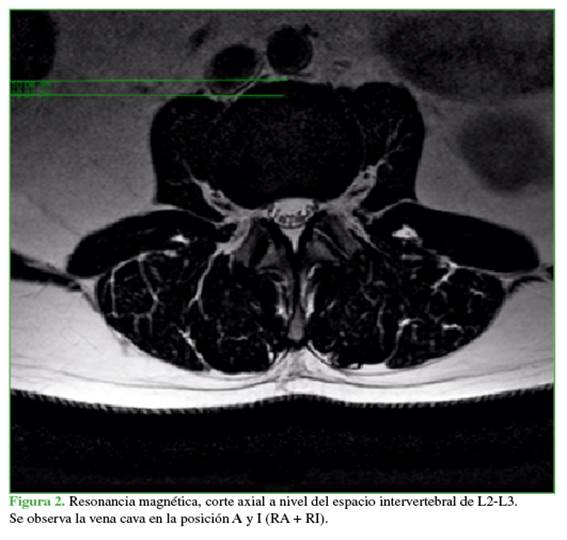

Se utilizó el método Moro17 que divide el espacio intervertebral en seis zonas que van de anterior a posterior (Figuras 1 y 2). El aspecto anterior del margen anterior del cuerpo vertebral fue definido como zona A; el aspecto posterior del margen posterior, como zona P; las zonas I, II, III, IV fueron distribuidas igualmente entre el margen anterior y el margen posterior, del anterior al posterior. La distribución de los grandes vasos abdominales en cada zona de cada espacio intervertebral lumbar fue analizada sobre la base de las imágenes de RM; el ancho del psoas en cada zona de cada espacio intervertebral lumbar de ambos lados se midió con el programa del análisis de imagen (PACS Carestream©). El espesor del psoas se definió como la distancia entre los puntos medios de los márgenes interior y exterior del psoas mayor en cada zona (Figura 3).

La vena cava en su recorrido por el nivel L1-L2 muestra una tendencia del 67,7% a la localización en el lado derecho, en la zona A (n = 111) y del 32,3% en el lado derecho, en la zona A y zona I (n = 53). En L2-L3, se observa una distribución del 51,2% (n = 84) a la derecha, entre la zona A y la zona I, mientras que el 48,8% (n = 80) se localiza en el lado derecho, en la zona A. En L3-L4, el 68,3% (n = 112) se encuentra en la derecha, entre la zona A y la zona I; el 28,7% (n = 47), en la derecha, en la zona A; el 1,8% (n = 3) presenta la bifurcación en dicho nivel y el 1,2% (n = 2) está en el lado derecho, en la zona I. Por último, en L4-L5, el 73,2% (n = 120) presenta la bifurcación en dicho nivel; el 21,3% (n = 35), en el lado derecho, entre la zona A y la zona I; en el 2,4% de los pacientes (n = 4), se localiza a la vena cava en el lado derecho en la zona A; en el 2,4% (n = 4), en el lado derecho, entre la zona I y la zona II; en el 0,6% (n = 1) se ubica a la vena cava en el lado derecho, en la zona I (Figura 6).